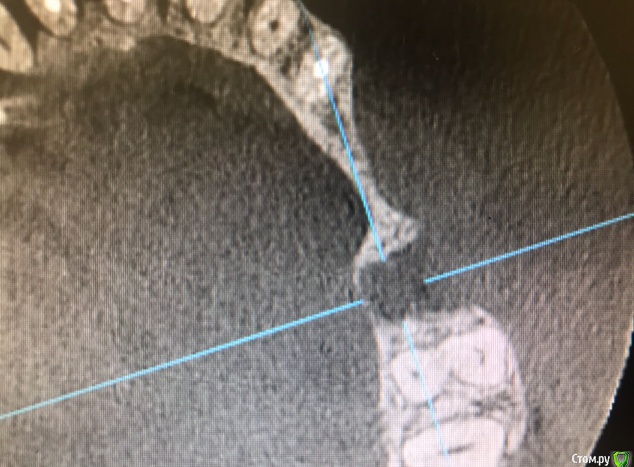

колесников Опубликовано 15 марта, 2019 Автор Поделиться Опубликовано 15 марта, 2019 Вот так выглядит интегрированый графт и соответственно не созревший. Время ожидания примерно равнозначное Ссылка на комментарий

колесников Опубликовано 16 марта, 2019 Автор Поделиться Опубликовано 16 марта, 2019 (изменено) Ну как бы тут все очевидно. Слева стала костью,справа нет. Но должен вам отметить,что даже в случае неудачи (как кажется)потери нет. Задача стояла не увеличить объём для имплантации или укрыть Имплант,а снять напряжение с вершины гребня и дать созреть десне. Имплант в нативной кости,он интегрирован,десна успела созреть за это время,возможно будет не так объёмно как хотелось бы,но у меня в запасе этап раскрытия ,фдм зарос ,есть с чем поработать. Все что не интегрировалось ,лизируется самостоятельно,выскребать ничего не нужно,ещё подождать. Изменено 16 марта, 2019 пользователем колесников Ссылка на комментарий